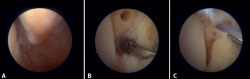

Figure 2. Anterolateral arthroscopic view of the right ankle. 1: talar dome; 2: anterior aspect of the tibia; 3: fibula; 4: distal fibers of the anterior tibiofibular ligament; 5: anterior talofibular ligament.

Figure 3. Anterolateral arthroscopic view of a right ankle on entering the tibiotalar zone. 1: talar dome; 2: articular aspect of the tibia; 3: fibula; 4: distal tibiofibular joint; 5: distal fibers of the anterior tibiofibular ligament.

Figure 4. Posterior arthroscopic view of a right ankle in which a symptomatic Stieda process has been resected. 1: posterior tibiofibular ligament; 2: transverse ligament; 3: talar dome; 4: distal tibia; 5: posterior subtalar joint; 6: flexor hallucis longus.

Twenty percent of the ATFL is intra-articular(7). On adopting an anteromedial access of the ankle, directing the arthroscope laterally, we can see the distal fibers of the ATFL with their oblique distribution and their continuation with the anterior talofibular ligament (Figure 2). If we move into the tibiotalar joint, we see the distal tibiofibular joint with the syndesmotic recess occupied by synovial tissue (Figure 3).

Posterior arthroscopic view

From the posterolateral approach we identify the lateral (fibular) malleolus and, from here, we visualize the intra-articular fibers of the PTFL, which run obliquely and insert into the distal portion of the tibia. We also see the distal thickening of the PTFL (transverse ligament) in continuity with the posterior lip of the distal tibia (Figure 4).